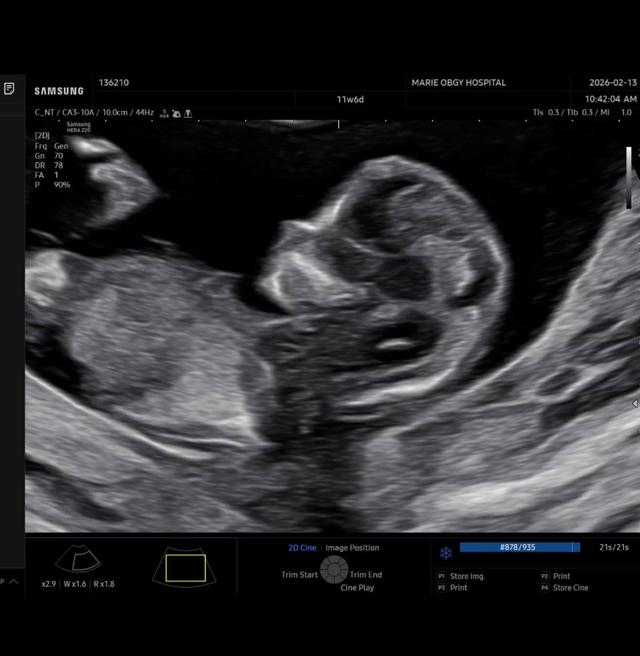

사진=김무영 SNS

17일 김무영은 자신의 SNS에 “우리 가족에게 찾아온 또 하나의 선물, 루이와 루디에 이어 세 번째 기적이 찾아왔습니다”라는 글과 함께 초음파 사진을 공개했다.

이어 그는 “아직은 누굴 닮았는지, 성별이 무엇인지 모든 게 신비롭기만 하네요. 건강하게만 만나자, 우리 막내야!”라고 덧붙였다.